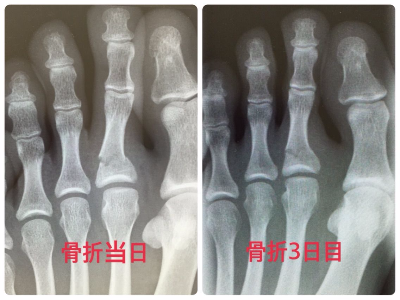

嘔吐下痢(ノロウイルス、ロタウイルス等)、風邪、急な発熱、熱中症等の内科的疾患、小児科も診察できますし、骨折や捻挫などのケガや子供の肘内障(肘が抜ける)の整復(肘を入れる)できます。

交通事故による痛み、むちうちの症状、首の捻挫(頸椎捻挫、むちうち、首の痛み)、腰の捻挫(腰椎捻挫、腰の痛み)、けが、切り傷、打ち身(うちみ)、打撲、捻挫(ねんざ)、骨折、脱臼、やけど、ぎっくり腰、肉離れ等後遺症で悩まれている患者様をトータルで治療し、保険(自賠責保険、労災保険等)にも対応している整形外科病院です。